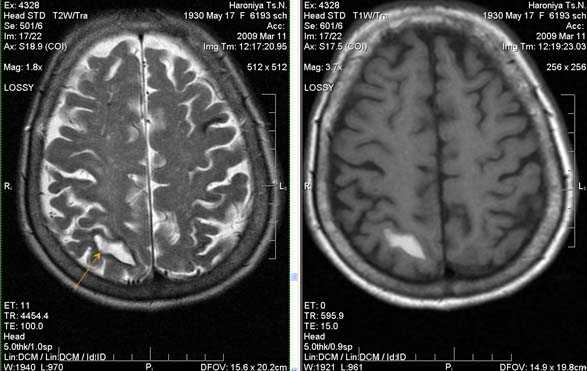

Одно из преимуществ МРТ в оценке последствий инсульта - возможность визуализировать нисходящую Валлеровскую дегенерацию аксонов в стволе мозга и кортико-спинальном тракте на стороне поражения.

Постишемическая лакунарная киста с перифокальным глиозом (средняя треть corona radiata справа)

Внутримозговая гематома, поздний подострый период (14-21 день) с перифокальным отеком вокруг гематомы.

Внутримозговая гематома правой теменной доли. Граница поздней подострой и ранней хронической стадии. В Т2-ВИ виден ободок гемосидерина (стрелка).

Хочется подчеркнуть возможность МРТ в выявлении последствий геморрагического поражения - остается хорошо дифференцируемый по Т2 ободок гемосидерина, недоступный для визуализации при других методах нейровизуализации.

Стрелками показан ободок гемосидерина по периферии постишемической кисты.

Характерным проявлением ДЭП на МР-томограммах является наличие множественных очагов глиоза.

В белом веществе левой лобной и обеих теменных долей, преимущественно субкортикально, выявлены множественные мелкие очаги хронической ишемии (большинство локализованных в бассейне правой средней мозговой артерии).

Проявлением хронической ишемии является также развитие выраженных дистрофических изменений белого вещества паравентрикулярной локализации - лейкоареоз.

Выраженные дистрофические изменения белого вещества паравентрикулярной локализации - лейкоареоз.

Сочетание мультифокальных очаговых изменений с диффузной кортикальной церебральной атрофией.